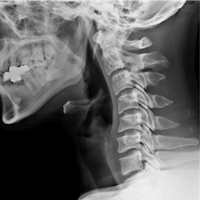

• 정상 경추 X-RAY

완만한 C자 커브

• 일자목 X-RAY

C자 커브 소실

• 거북목 X-RAY

역 C자 커브